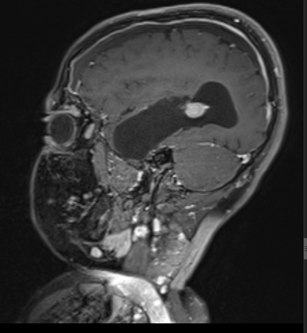

MRI outside hospital was done which was re-reported in our centre as Bilateral temporal lobe enhancing lesions. The left temporal lobe mass was larger in size and causing right-sided midline shift causing compression of the third ventricle with upstream hydrocephalus and transependymal seepage. These masses were reported as of neoplastic etiology, likely low-grade gliomas. Then MRI Brain with contrast was repeated which showed Bilateral intraventricular masses which are more or less stable in sizes causing hydrocephalus and compression effect at the level of the third ventricle towards the right side. Differentials included intraventricular tumors. No adjacent invasion is seen.

Post op MRI was done after 24 hours and it showed post-surgical changes of left temporal craniotomy with left temporal and subarachnoid hemorrhage. Pneumocephalus was noted along the left subarachnoid space and left frontal lobe, causing mild effacement of the ipsilateral gyri. Moreover, there was a redemonstration of enhancing right temporal lobe mass with enhancing lesion is noted in the left lateral ventricle suggestive of residual disease.

Figure 3: Lesion on T1 post contrast sagittal brain MRI.

The mean age of onset with nodal disease is 20.6 years with a male to female ratio of 1.4:1 [6,17]. Patients who develop intracranial involvement, however, become symptomatic at a mean age of 34.9 years, with a strong male preponderance. In intracranial RDD, the most involved structures are the suprasellar region, cerebral convexity, parasagittal region, cavernous sinus, and petroclival region [18,19]. Radiologically, the typical MRI findings include isointense to hypointense T1-weighted signals and hyperintense T2-weighted signals with homogeneous enhancement post-contrast. Bitemporal lesions often exhibit a dural-based, meningioma-like appearance [20]. Intracranial RDD is commonly confused with meningioma and requires tumor histopathology and immunohistochemistry for its definitive diagnosis.